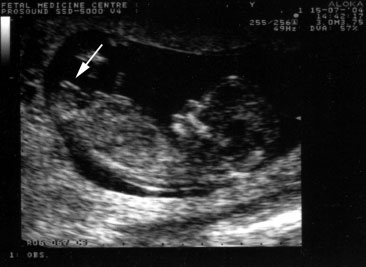

As the ultrasound was performed, Meera felt a sense of relief wash over her. The scan was non-invasive, quick, and provided her with the answers she had been seeking. The clarity she received about her health was invaluable. With this newfound knowledge, Meera was able to address her health proactively, consulting with her gynecologist on the next steps.